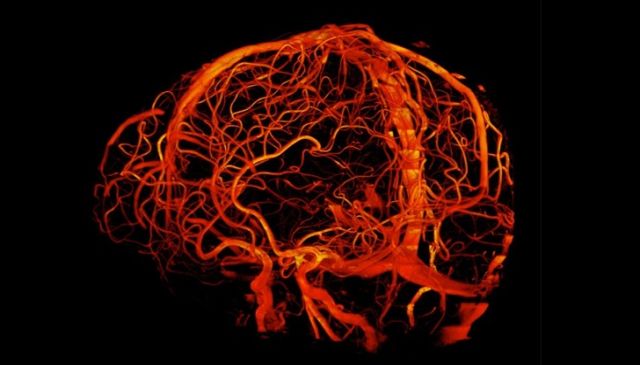

使用断层扫描仪拍摄的大脑血管照片。